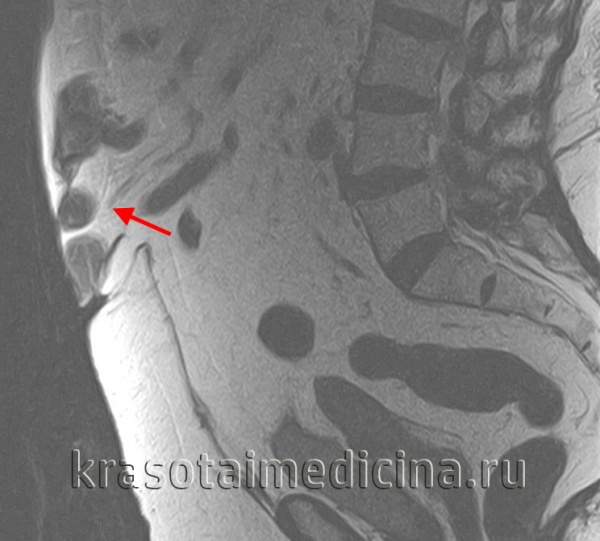

МРТ ОБП и забрюшинного пространства. Грыжа белой линии живота выше пупка (сальник, брыжейка, часть тонкой кишки)